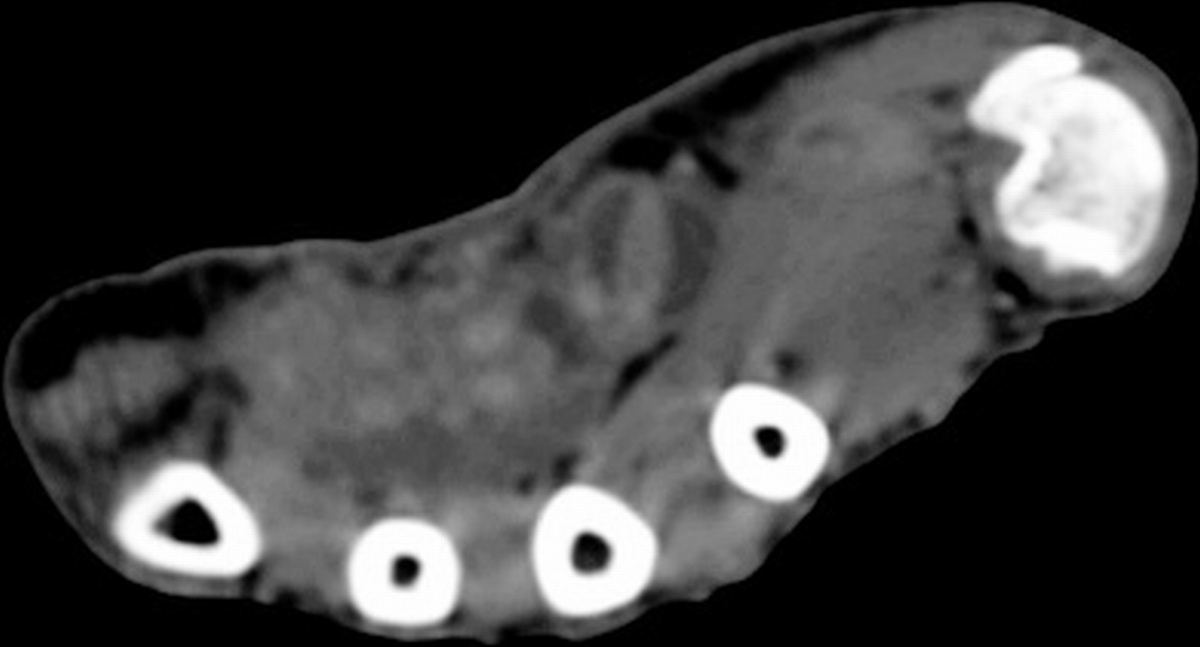

The radiologist  interpreted his MRI as normal, but these views show bulky, edematous flexor synovitis.